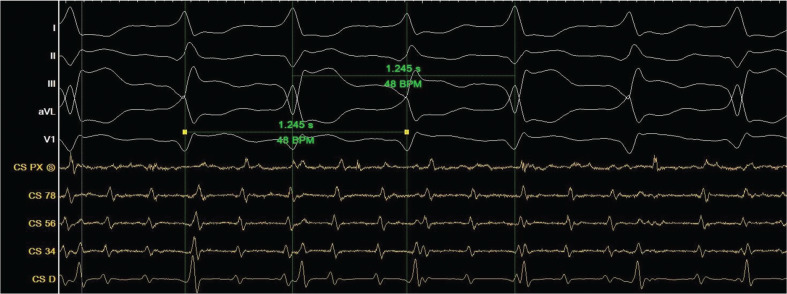

Bidirectional ventricular tachycardia (VT) is a rare arrhythmia characterized by alternating QRS morphologies and axis changes. Atrial flutter (AFL) can coexist with ventricular arrhythmias, complicating diagnosis. We present a case of a 56-year-old man with a history of ischemic heart disease and severe mitral regurgitation admitted with palpitations who was diagnosed with dual tachycardia (bidirectional VT and AFL).